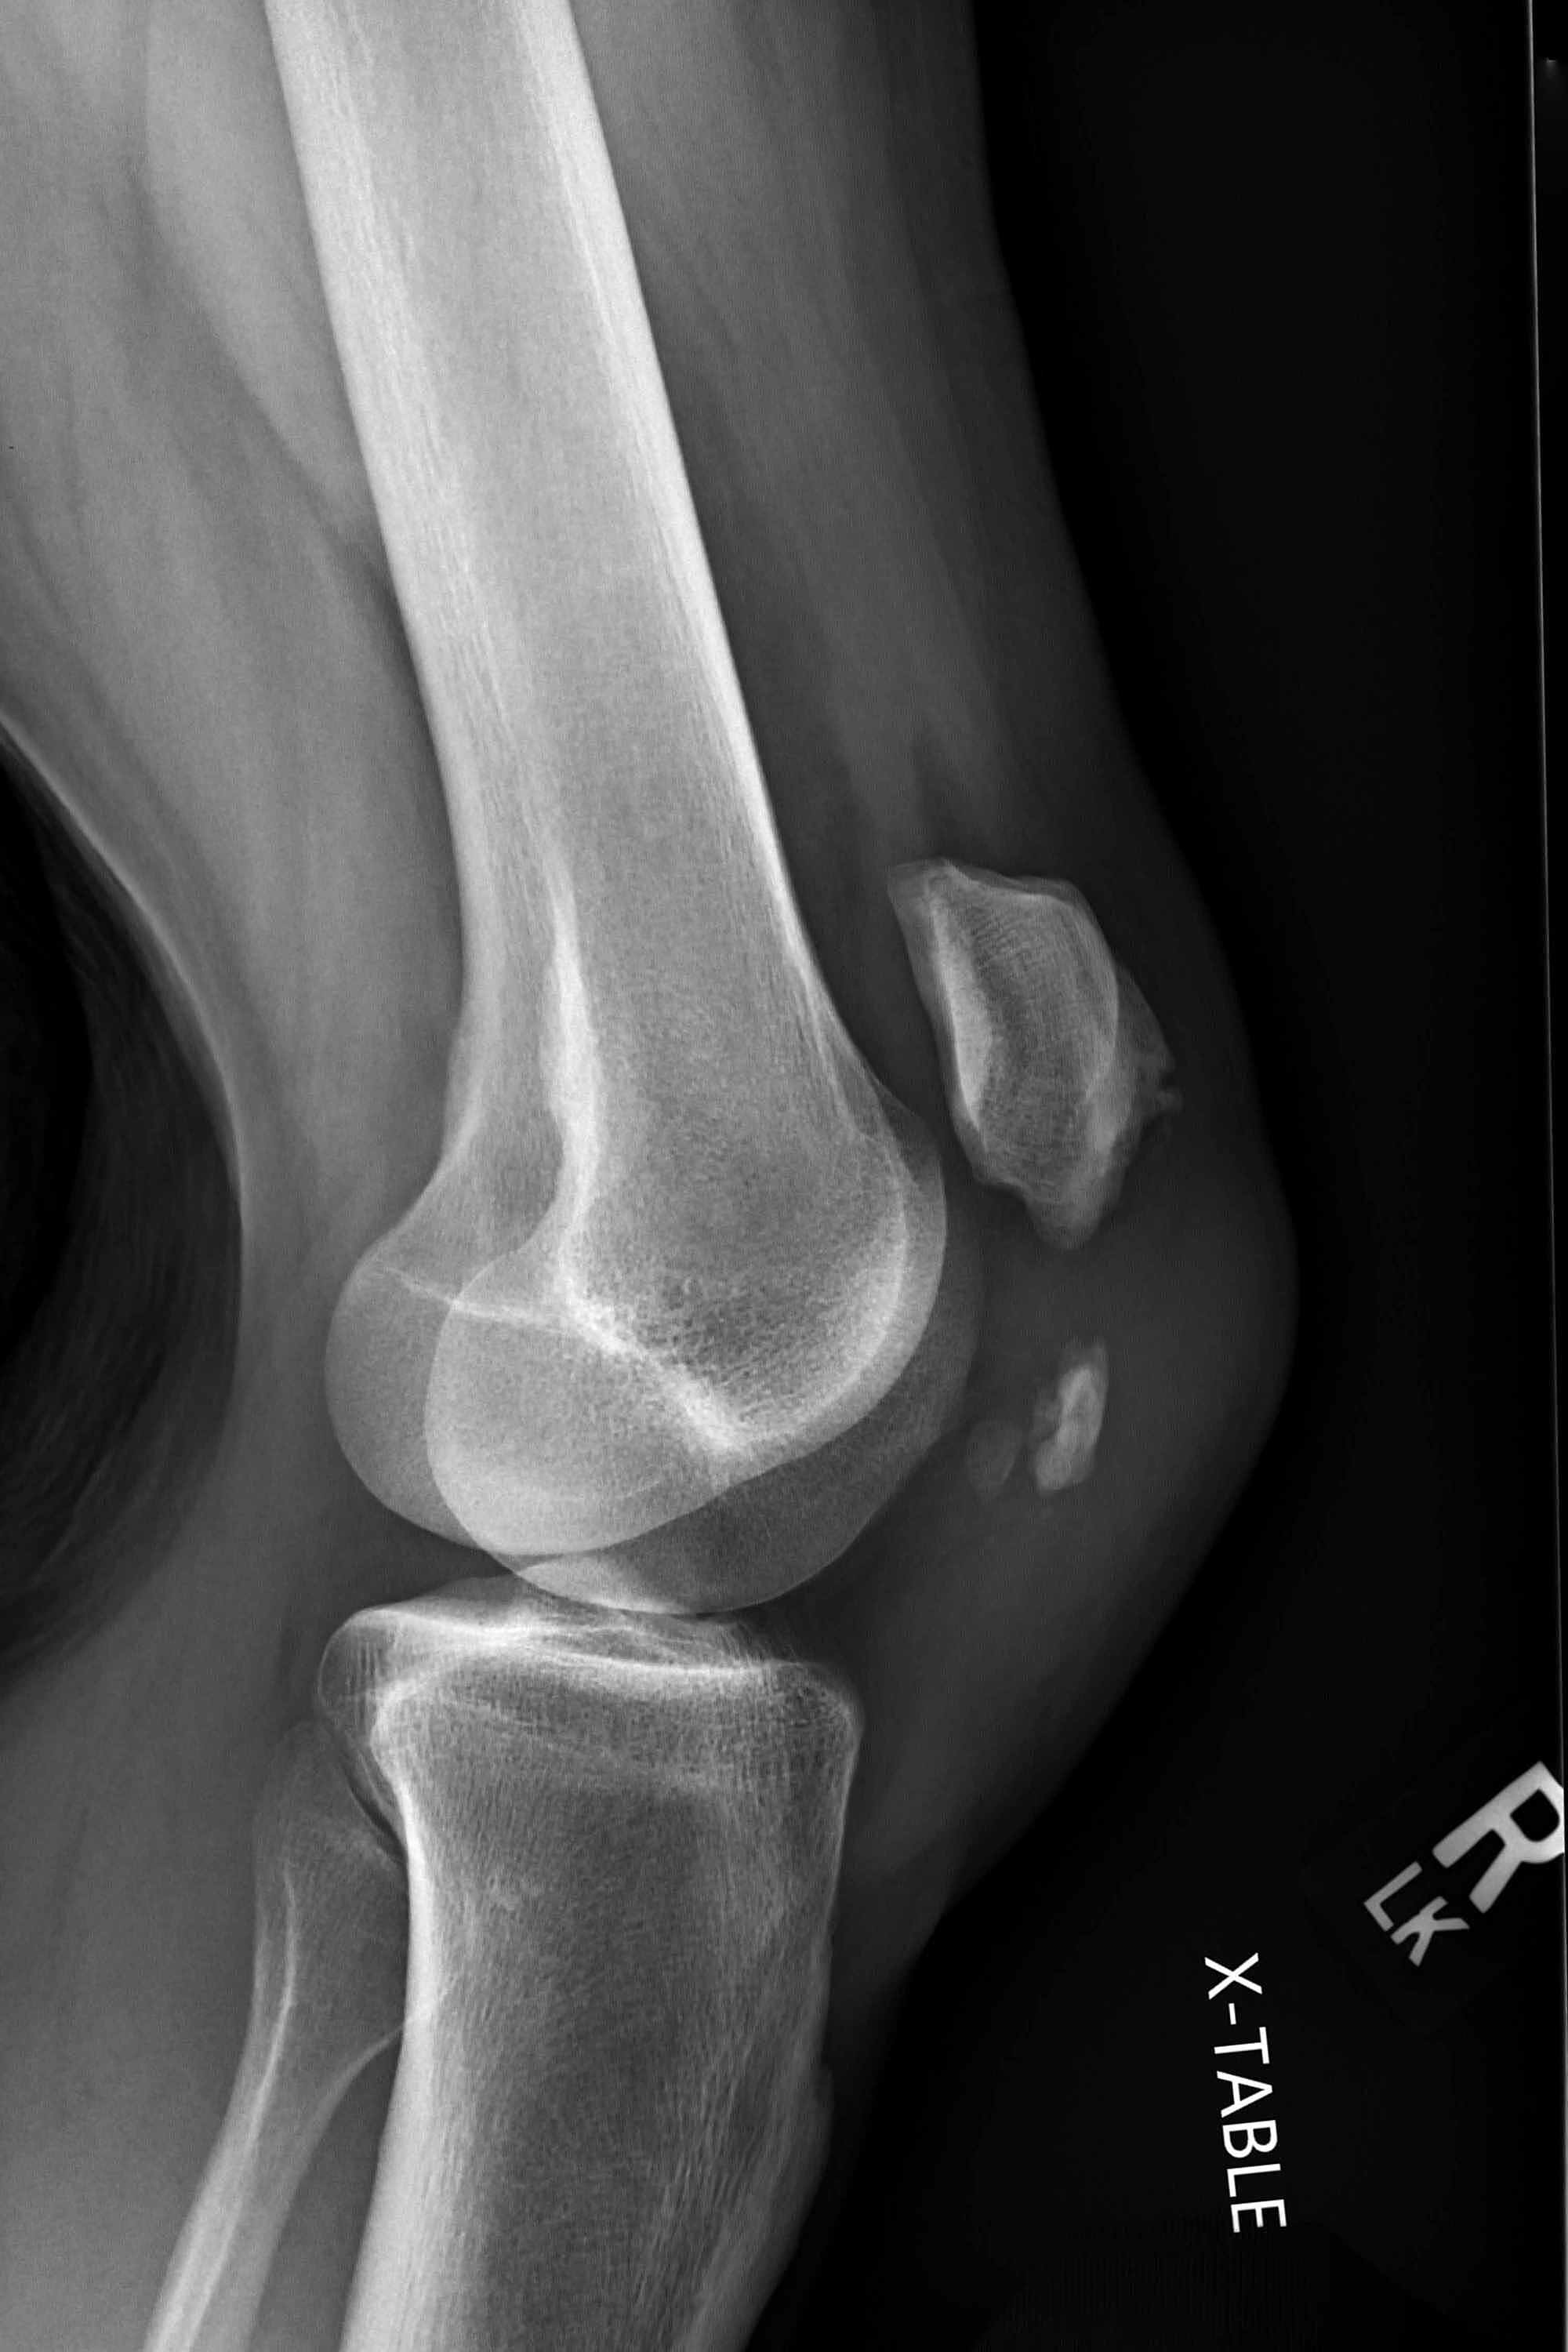

From www.researchgate.net

Preoperative Xrays of a comminuted patella fracture (above). 3 months Return To Sports After Patellar Fracture For athletes, the journey back to the field, court, or track is fraught with hurdles, requiring more than just physical healing. After patella fracture most common complication is the knee stiffness. It was attempted to answer the following two questions: Patella fracture can be treated without surgery (if fracture is undisplaced) or with surgery (for displaced fracture fragments). (1) how. Return To Sports After Patellar Fracture.